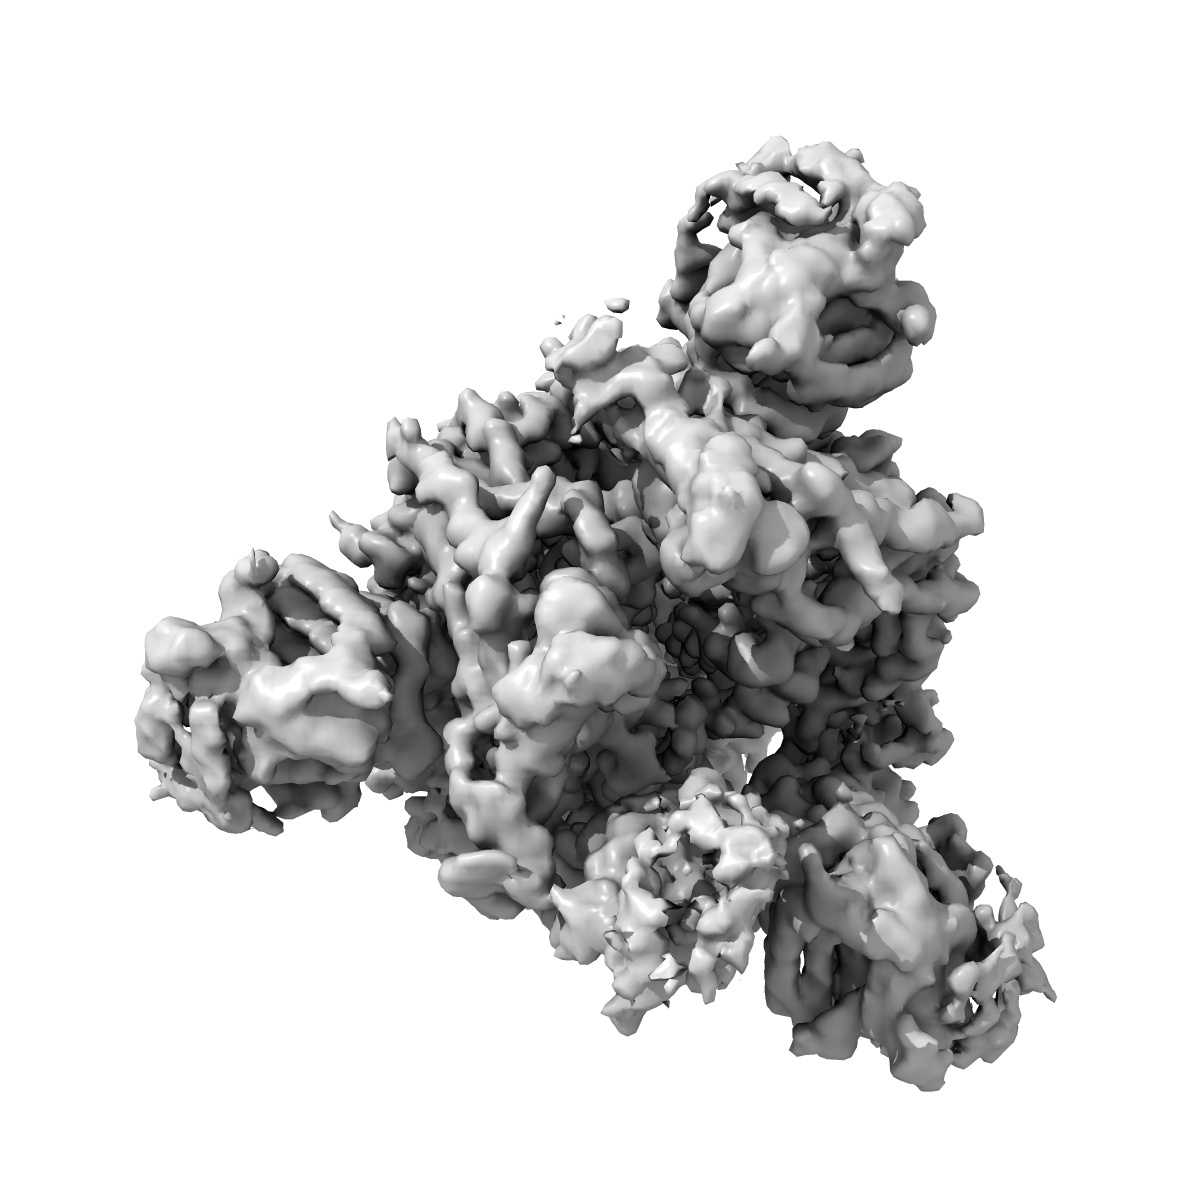

Single-particle

2.9 Å

Cryo-EM structure of SARS-CoV-2 S-Delta variant (B.1.617.2), one RBD-up conformation 4